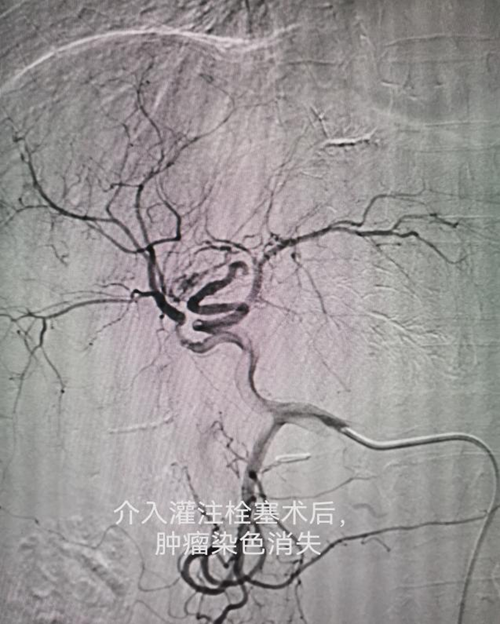

本门诊的核心特色在于融合了两大前沿技术:细胞与基因技术和介入微创技术。这一创新组合打破了细胞传统治疗的局限,结合介入技术,创新细胞精准递送方式,能够快速、高效、均衡将细胞灌注到肿瘤或者靶器官,实行更精确、更高效、无副作用治疗,同时针对疾病的根本病因,为每位患者量身定制“一对一”的个体化治疗策略,实现真正意义上的精准医疗。

车能雨教授病例展示:

病例一:刘先生,男,55岁,患肺癌,经过三次介入微创手术+三次细胞治疗+靶向治疗,肺癌缩小90%,全身脊柱转移灶得到控制硬化,全身剧痛消失,处于NED状态。

病例二:李女士,52岁,患胆管癌,经过一次介入微创治疗+三次细胞治疗+靶向治疗,胆管癌大部分消失,临床症状大部分好转,暂处于NED状态。(图文:何亮)